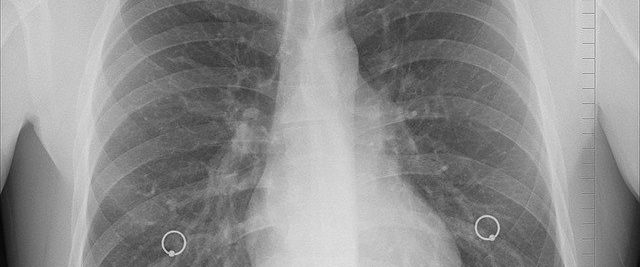

我们来科普一下这方面的常识:肺炎就是肺部发炎,影响的主要是肺泡——呼吸过程中气体交换的地方。肺炎通常会带来哪些症状、有哪些原因引起?

肺炎的症状主要是咳嗽、胸痛、发烧与呼吸困难。从轻微到严重不一,通常治疗后会好转,但痊愈后仍可感到疲倦。

某些特殊的肺炎还有特殊症状。如退伍军人菌引起的肺炎还可能有腹痛、腹泻或意识混乱;肺炎链球菌引发的肺炎,痰是锈色的;克雷伯氏肺炎菌引发的肺炎,痰是黑醋栗果冻样的血痰;霉浆菌性肺炎可能会伴有颈部淋巴腺病变、关节痛与中耳炎;病毒性肺炎比细菌性肺炎更容易产生呼吸急促。